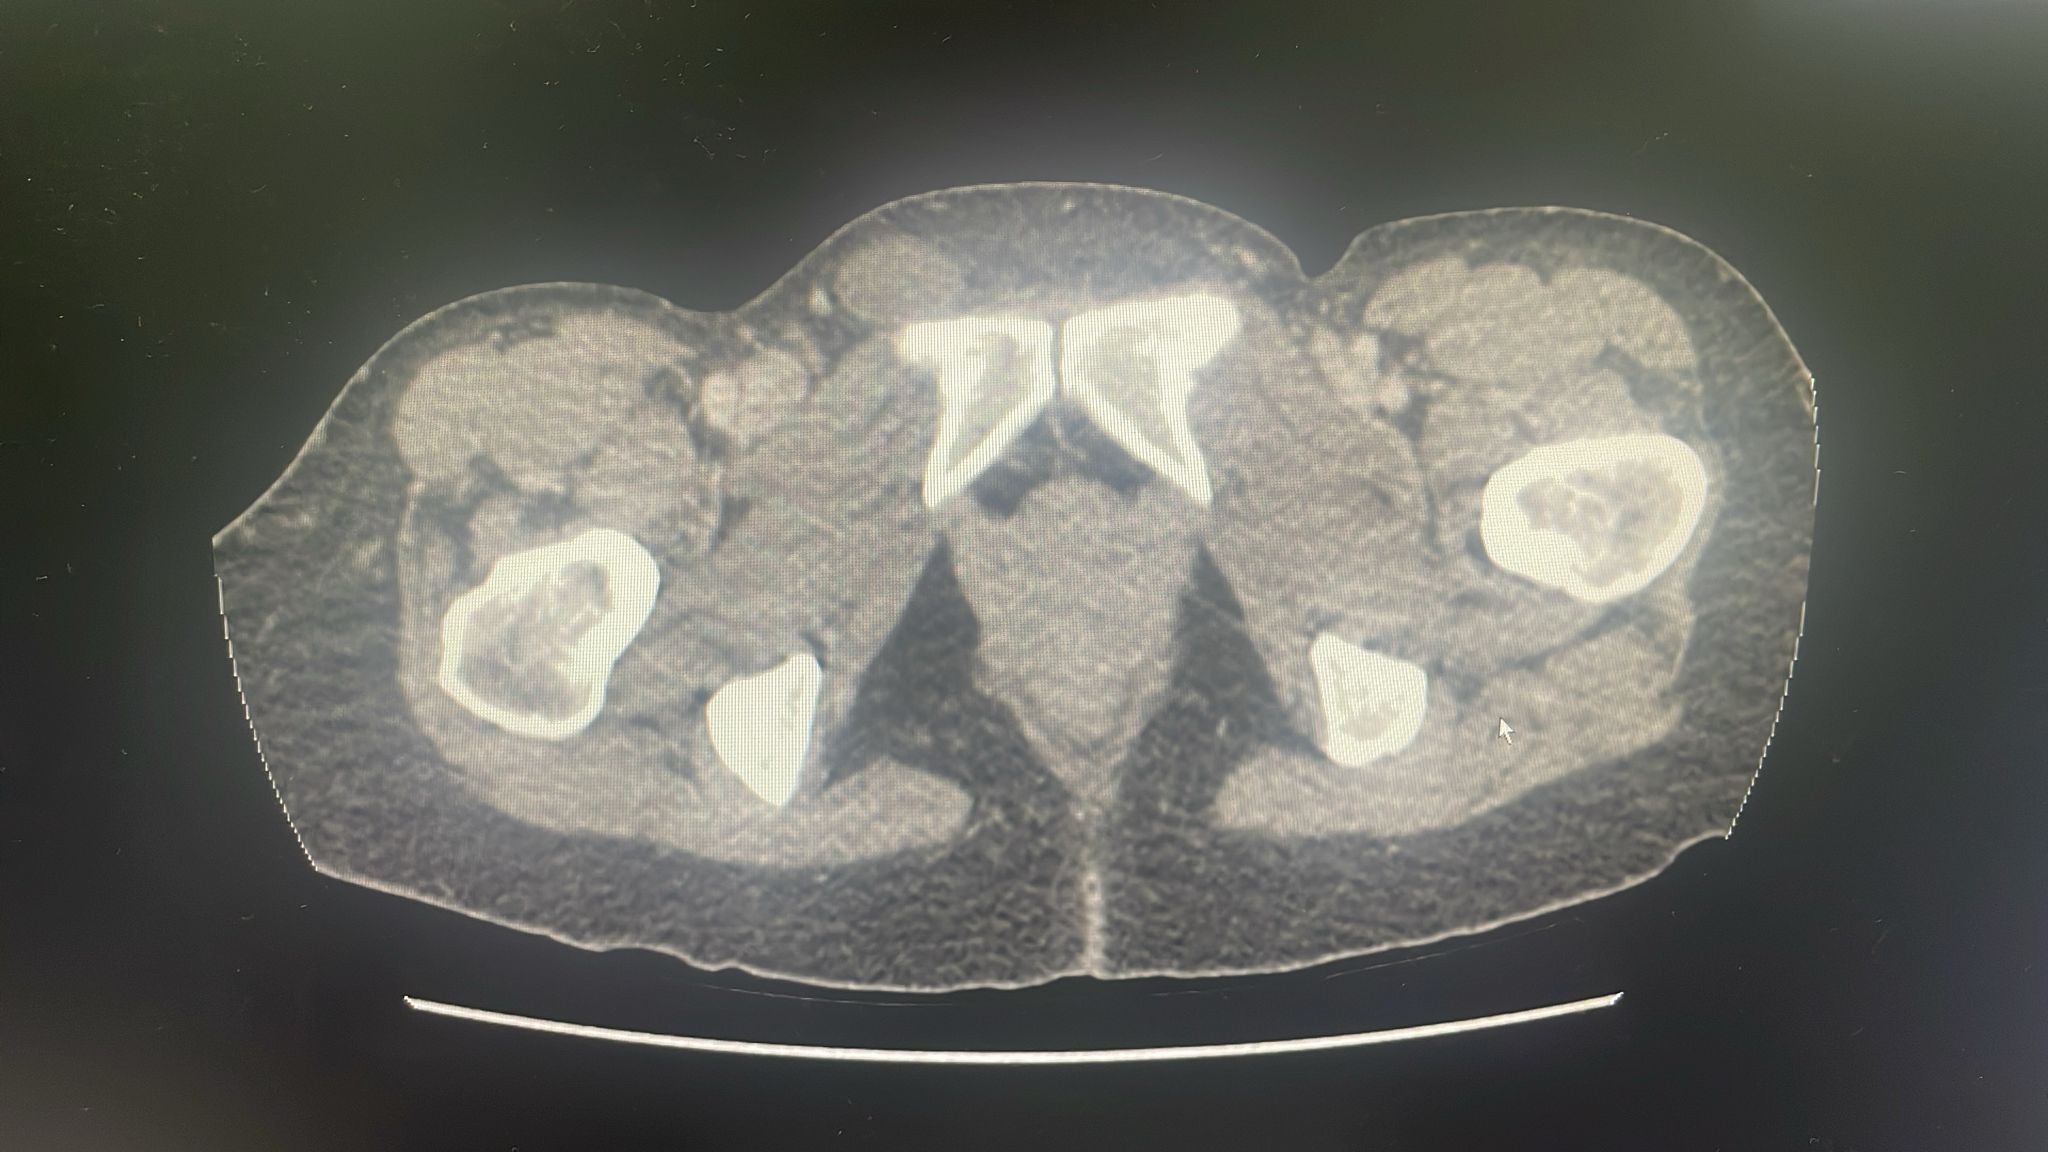

Dada la ausencia de dolor en tumoración inguinal, pero con la sospecha de obstrucción intestinal 2º a hernia inguinocrural derecha incarcerada, se decide realización de TAC abdomen, que confirma obstrucción intestinal con cambio de brusco de calibre en hernia crural derecha que contiene asa de íleon distal con hiporrealce parietal en su parte declive que podría traducir sufrimiento a este nivel.